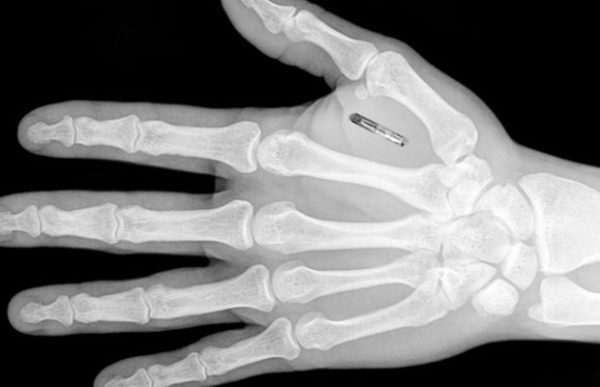

Изобретение носит название «спинномозговой интерфейс» и является крошечным имплантом, состоящим из двух чипов. Интерфейс был изобретен учеными Федеральной политехнической школы Лозанны (EPFL) в Швейцарии. С помощью него ученые смогли восстановить способность парализованных обезьян ходить и даже бегать уже через 2 недели после травмы.

В исследовании с обезьянами было использовано устройство, интерфейс которого состоит из двух чипов. Первый чип располагался в двигательной области головного мозга — там, где принимаются решения о движении.

Первый датчик выступал в роли приемника таких сигналов и передавал его по беспроводной сети на второй. Второй же располагался в области травмы, то есть там, где нервный сигнал из-за травмы не проходит.

Сигнал от одного датчика к другому пропускался через компьютер, который кодировал сигнал и передавал его дальше по нервам. Этот интерфейс восстанавливал работу нервной системы и передачу нервного сигнала, что возвращало способность к движению.